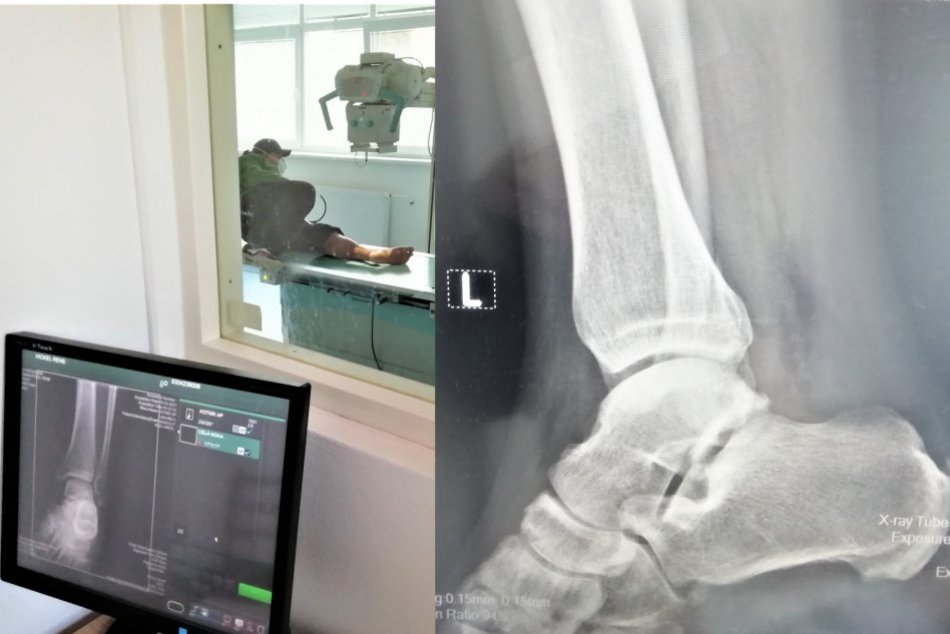

Ilustračný obrázok k článku Na röntgenológii v Moravciach sa nenudili: Vlani zrealizovali 10-tisíc vyšetrení

Zdroj: AGEL SK

Röntgenologické oddelenie zlatomoraveckej nemocnice prešlo komplexnou rekonštrukciou v roku 2018.

„V rámci nej sme obstarali a inštalovali úplne nové skiagrafické röntgenologické zariadenie s priamou digitalizáciou. Súčasťou modernej technológie v hodnote 126 000 eur je aj systém pre archiváciu obrazu a komunikáciu,“ uviedla Horniaková.

Nové RTG zariadenie nemocnica spustila do prevádzky v apríli 2018.

Za minulý rok na ňom absolvovalo vyšetrenia vyše 9 800 pacientov, z toho bolo takmer 1 050 detí. Špeciálny röntgen je využívaný pre potreby hospitalizovaných i ambulantných pacientov.